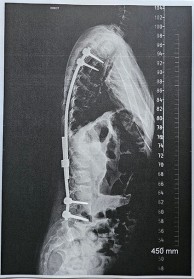

Kiara had spinal surgery to insert growth rods. Kiara explains that this helps keep her spine straighter while she grows. She will go back to RNOH about every six months for the next four to five years to have the rods lengthened. When she has just about finished growing, Kiara will have spinal fusion surgery to complete her treatment.

“The doctors said the curve in my back was 81 degrees, which is very big,” Kiara says. They decided that growth rods would work best, with a staged treatment plan to make sure she could stand, move around easily and keep growing properly.